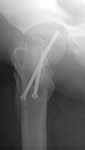

1 year ago a female 44 y.o. was operated on the femoral shaft and neck fractures 2 weeks after a car accident. Closed interlocked nailing was performed, and the neck was fixed miss a nail with poor result mostly due to her obesity - femoral circumference is >80 cm (image 1).

This is a good example of sub optimal placement of the neck screws. Young patients with neck/shaft combo fxs have a high Pauwel's angle. This is counteracted by open reduction and internal fixation in order to reduce caudal portion of fem neck. the screws are angled differently by placing them perpendicular to the fem neck fx line (typical AO technique) or horizontal to the floor. The screws here are similar to elderly fem neck fx types. Therefore, no biomechanical advantage exists and the nonunion is produced.